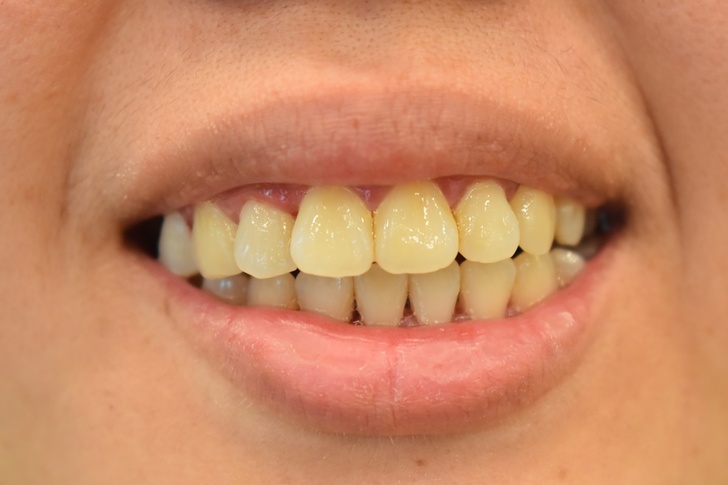

▲洗牙後的牙齒乾乾淨淨,還被稱讚牙齒其實很好看,真是有夠害羞的~~

不過要敢開口大笑,還是要把缺牙補好,才不怕被人看到少一顆牙。